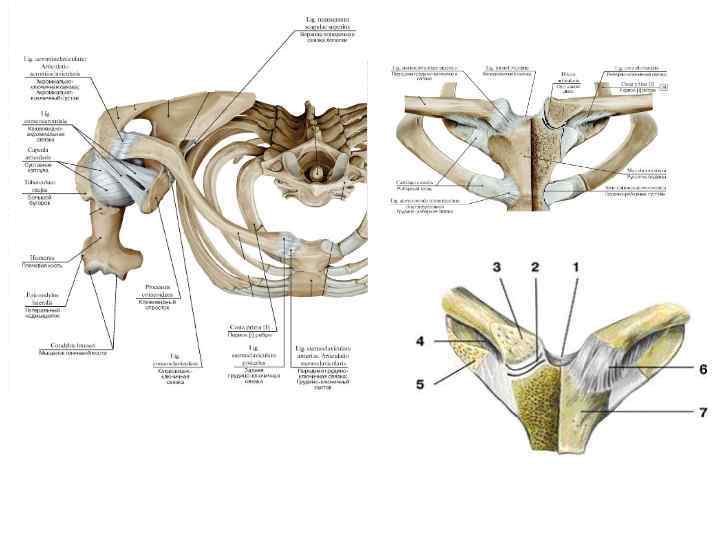

Анатомия малого таза: детальные схемы и изображения